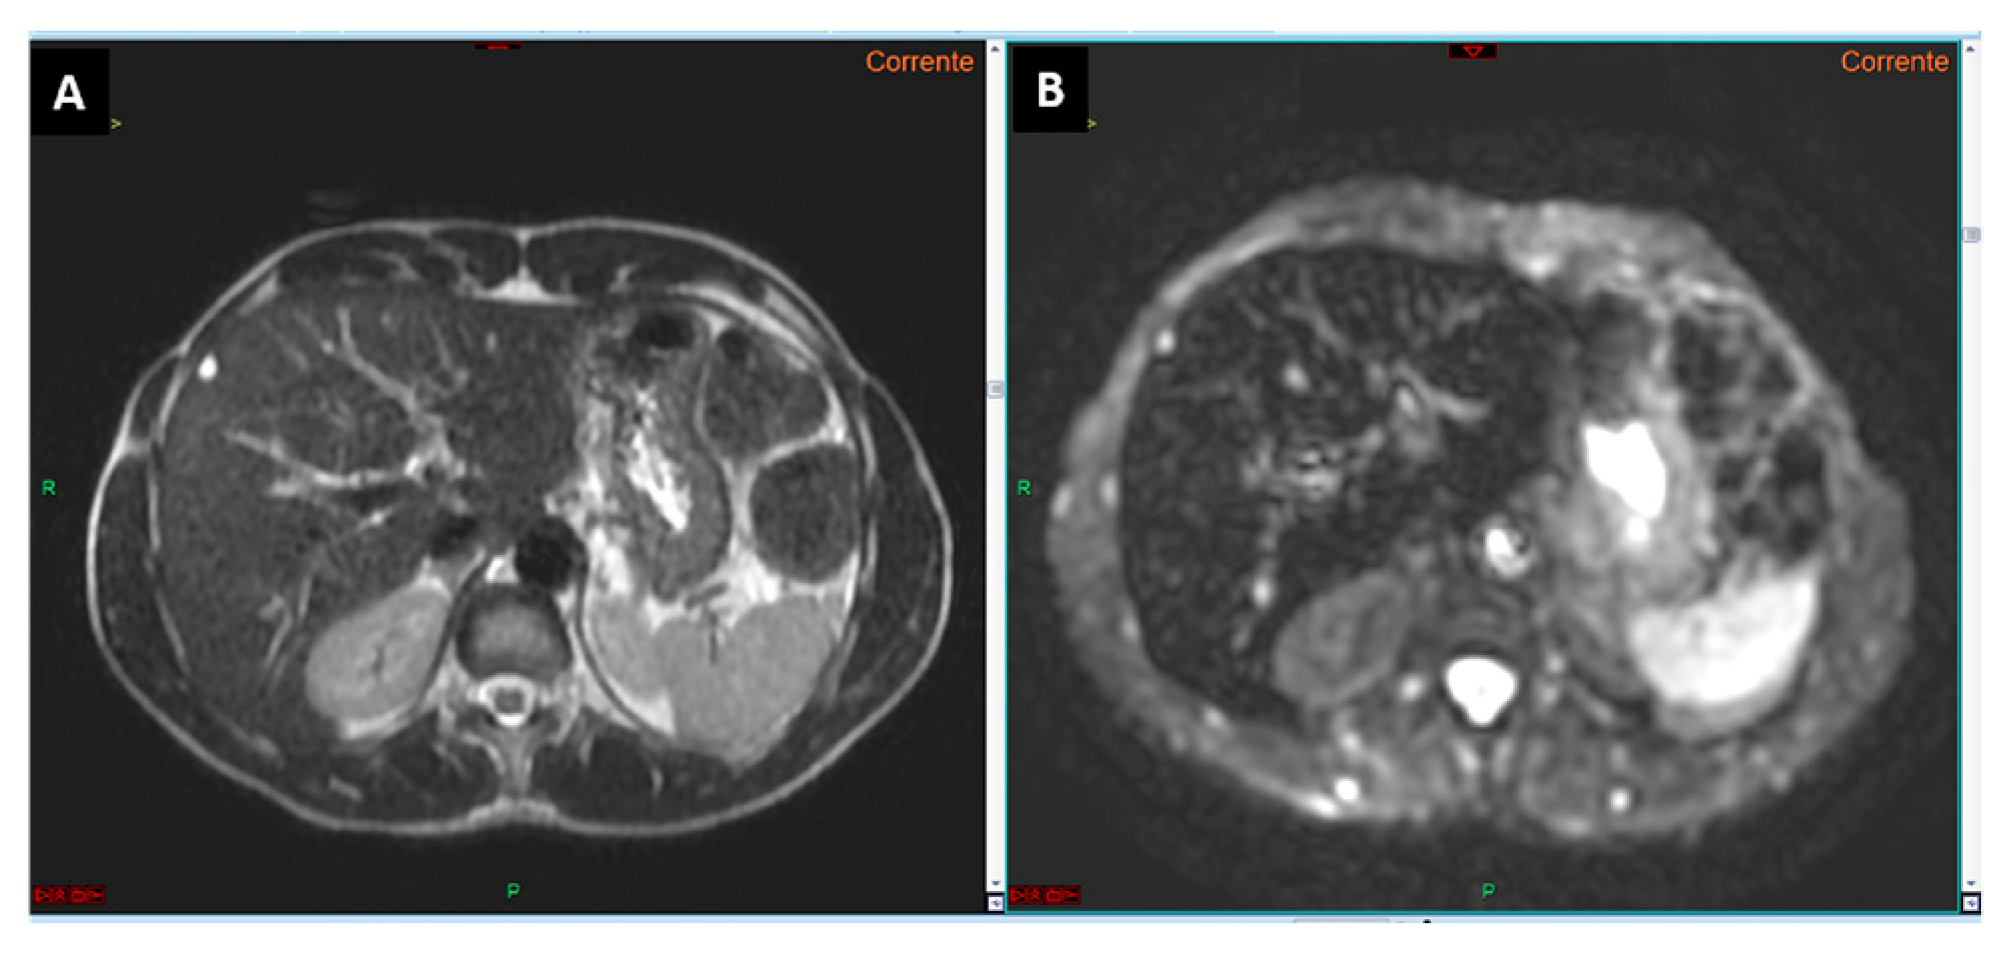

- Non-contrast aMRI (NC-aMRI): This protocol includes T1 in-phase and out-of-phase sequences, T2-weighted sequences, and diffusion-weighted imaging (DWI) with b0 and a single high b-value;

- Hepatobiliary phase (HBP) aMRI (HBP-aMRI): This protocol uses hepatospecific contrast agents, with imaging performed approximately 20 min post-injection. It includes T2-weighted sequences, DWI with b0 and another single high b-value, and the hepatobiliary phase.